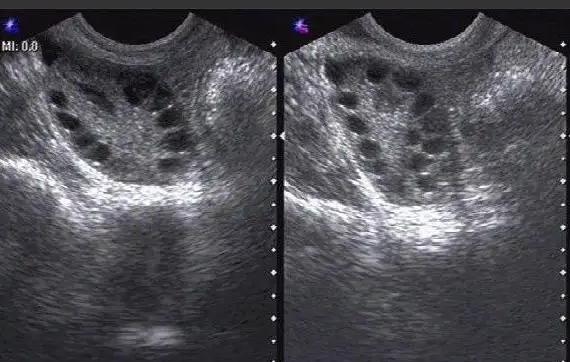

监测卵泡的时候之所以要压肚子是因为通过b超还没看见卵巢,可能是被盆腔内的肠气给挡住了,所以就要压一下肚子。女性积极配合医生做检查即可,如果有什么疑问,也可以咨询一下医生。如果发现有优势卵泡排出,就可以合理同房,增加怀孕几率。

卵泡监测指用B超来连续检测身体卵泡发育、排卵的情况,通过得到的数据来看女性身体是否有卵泡发育问题、排卵方面的障碍。医生做卵泡监测每次要让患者按压住肚子那样会看的清楚些,卵巢是质软的并且其前方的组织器官也是软的,能够缓冲,所以B超的检查不会对这个卵巢和子宫造成伤害的。